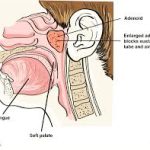

Pediatrik hastada adenoid hipertrofisi (yani adenoid dokusunun normalden fazla büyümesi), orta kulak ventilasyonu üzerinde önemli etkiler yaratır. Bunun temelinde anatomik ve fizyolojik mekanizmalar yatar. Aşağıda adım adım açıklıyorum:

Östaki borusu, burun ve orta kulak arasında yer alan bir kanaldır ve orta kulağın havalanmasını, basınç dengelenmesini ve salgıların drenajını sağlar.

Çocuklarda Östaki borusu daha kısa, daha yatay ve daha dar olduğundan, tıkanmaya daha eğilimlidir.

Adenoid dokusu nasofarenkste, Östaki borusunun açıldığı bölgeye yakın bulunur.

Östaki borusunun farengeal açıklığı direkt olarak mekanik olarak tıkanır.

Bu tıkanma, orta kulakta negatif basınç oluşmasına ve sıvı birikmesine (otitis media effüzyon) yol açar.